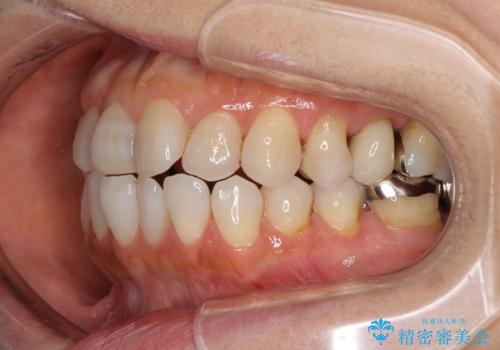

前歯の突出感と上下の隙間 インビザラインによる矯正治療

- 前歯の上下スペースと前歯の隙間を気にして来院された患者様です。

インビザラインにより上下の前歯の隙間を閉じながら、IPRを用いて口元の突出感を合わせて改善していくこととしました。

上下の隙間に舌が入り込むことが、すきっ歯やオープンバイトの原因であったため、舌の筋肉のトレーニングも並行して行い、後戻りの抑制を図りました。